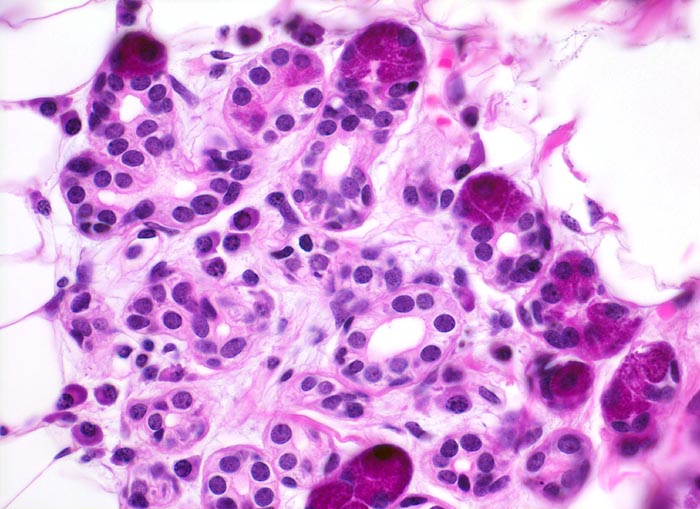

Normale Glandula Parotis: Acini und Streifstücke

Die Acini der rein serösen Speicheldrüse bestehen aus einem Zelltyp mit feingranulärem PAS positivem Zytoplasma. Die Schaltstücke gehen aus den Acini hervor. Sie werden von einem kubischen Epithel mit zentralen grossen Kernen ausgekleidet. Im lockeren Stroma zwischen den Acini liegen einzelne Plasmazellen.